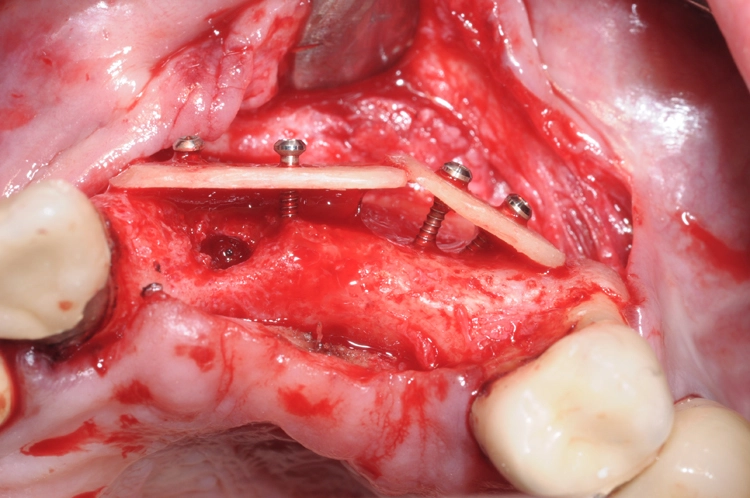

Die Entscheidung fiel daraufhin auf ein zweizeitiges Vorgehen mit vorheriger Knochenaugmentation in Schalentechnik und späterer Implantation von zwei BLT-Implantaten mit augmentativem Relining: Der Patient entschied sich nach ausführlicher Beratung und Vorstellung der alternativen Augmentationsmöglichkeiten für die Schalentechnik mit allogenen Kortikalisplatten und Granulaten (maxgraft® spongiosa, Straumann), wie die Abbildungen 4 bis 7 dokumentieren.

Nach einer viermonatigen Einheilphase erfolgte die Implantation von zwei Straumann® BLT Implantaten mit einer Länge von 12 mm und einem Durchmesser von 4,1 mm im Bereich des aufgebauten Knochens (Ausgangssituation siehe Abb. 8). Vor der Implantation fand vorbereitend eine Glättung der Oberfl äche statt, um scharfe Kanten zu beseitigen (Abb. 9). Für die korrekte prothetische Positionierung der Implantate kamen individuell gefertigte Orientierungsschablonen zum Einsatz, anschließend wurden die Implantate für eine verschraubte Brücke gesetzt (Abb. 10).

Die Abbildungen 11 und 12 dokumentieren das augmentative Relining, das zum Schutz vor Resorption und zur Konturaugmentation dienen soll. Dabei wurde eine Schicht bovines Knochenersatzmaterial (Straumann® XenoGraft) direkt auf den neu aufgebauten Knochen aufgetragen und mit Hilfe einer Kollagenmembran (Jason® membrane, Straumann) konturiert und vernäht. Damit legt man dem darunterliegenden neu aufgebauten Knochen einen Schutzpanzer an, der ihn einmal mehr vor Resorption schützt und die weitere Regeneration begünstigt.